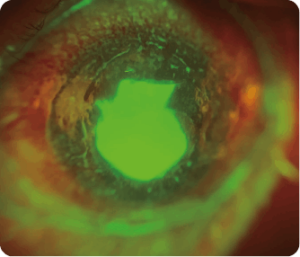

Oftalmoloji teşhisinde görüntülemenin giderek daha önemli bir rol oynadığı kabul edilmektedir. Spectrum Adaptör, özellikle ön segment görüntüleme için tasarlanmış bir akıllı telefon adaptörüdür. Optometristler, pratisyen hekimler, çocuk doktorları, veteriner hekimler vb. için temel göz muayenesi talebini karşılamak üzere 10x büyütme sağlar. Özel olarak tasarlanmış optik lens, Spectrum Adaptör’ün birinci basamak göz muayenesi ve teletıp için net ön görüntüler yakalamasını sağlar. Bu sayede, profesyonellerin etkili bir şekilde önleyici bakım ve teşhis yapmalarına olanak tanır.

Image Showcase